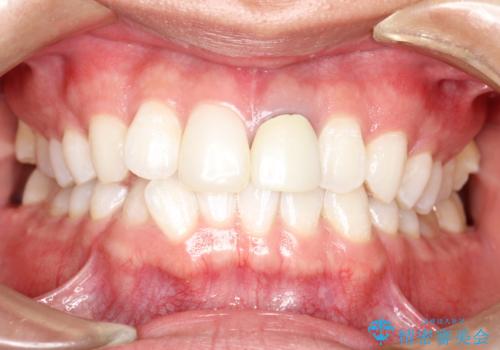

- 初診時には上顎前歯の突出、前歯部の深いかみ合わせ、叢生が見られる状態でした。

インビザラインにて不正咬合の原因除去を行うシミュレーションを念入りに制作の上、治療を行いました。

使用したインビザラインのマウスピース枚数:42枚+25枚+22枚(初回マウスピース+リファインメントが2回、1週間に1枚ペースでの交換)

このケースでは非抜歯にて奥歯を後方に移動させる事で前歯の突出を改善するスペースを作り出していますが、これはマウスピースと顎間ゴムの併用によるもので、患者様のご協力の賜物と言えます。

深い噛み合わせについてはシミュレーション上の結果と、予期される実際の歯の移動量とを考慮し、特殊なセットアップを行う事で望ましい結果を得ることができました。

治療途中でリファインメントという追加のマウスピースを製作する手順を行っていますが、その際に上下の正中を合わせたいとの要望があったため、追加シミュレーションの際に追加でセットアップを施しましたが、無事、上下の正中もご要望通りに改善しています。

使用した装置はマウスピースと顎間ゴムのみです。ワイヤーやマイクロインプラントなど補助装置の使用はありません。